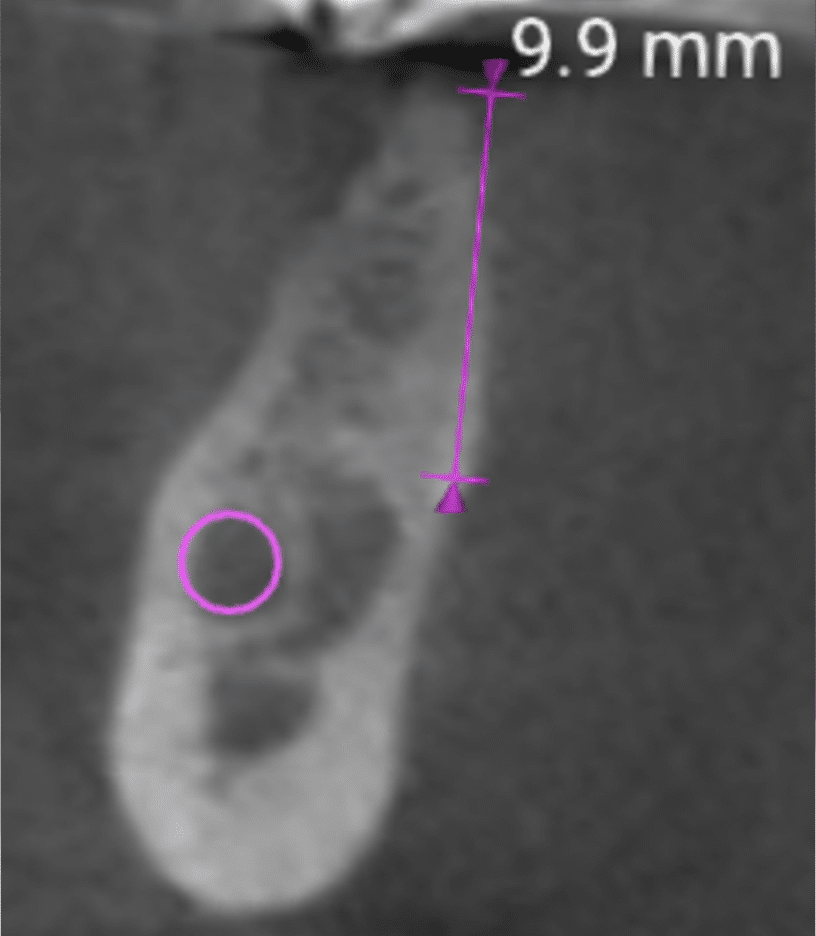

Ma perché c’era tanto oro nella bocca dei prigionieri? Per capirlo, è necessario fare una premessa storica sull’odontoiatria dell’epoca.

L’oro era, all’epoca, il principale materiale per la ricostruzione dei denti. Era utilizzato per otturazioni, corone e ponti. Dal punto di vista della durata è considerato tuttora il materiale migliore in assoluto.

Inoltre, la comunità ebraica comprendeva molti ottimi dentisti, che usavano, appunto, perlopiù oro.